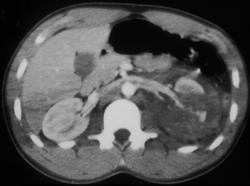

Renal Laceration With Contrast Extravasation on Delayed Scan